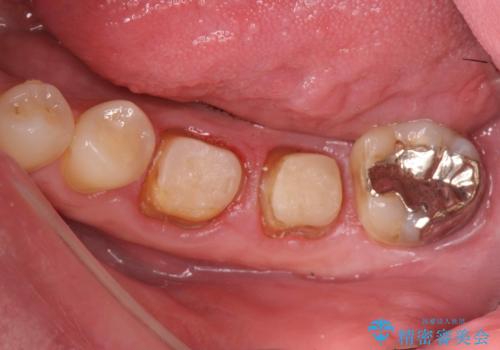

- 銀歯・虫歯・治療途中の歯を治していきたい、セラミックの歯にしたい!と希望され来院されました。

銀歯の下で再発した虫歯や、根尖病変等、多々の問題が認められましたがひとつづつ丁寧に改善し、長期的な予後の見込めるセラミック治療を行っていきます。